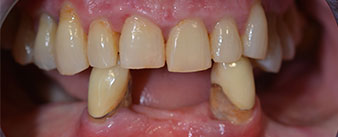

Пациентката е 64-годишна жена с частично обеззъбяване на зъби 38, 33 и 43 и частична долночелюстна протеза (Фиг. 1 и 2).

частично обеззъбяване

Фиг. 1

Фиг. 2